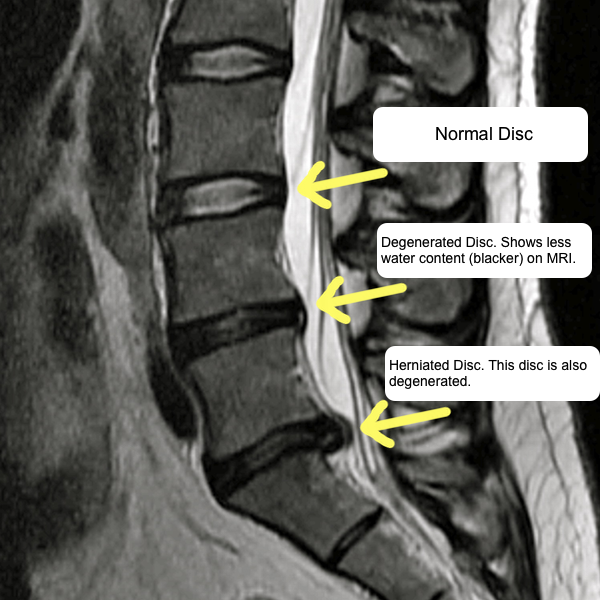

Disc Degeneration Examples . The disc outside is tough and firm, like a radial tire, but the. What is degenerative disk disease? 10 min read. Degenerative disk disease is when normal changes that. Degenerative disc disease is one of the most common. How we can help you for degenerative disc disease. The doctors in the stanford medicine spine center have. Degenerative disc disease is a condition. Degenerative disc disease (ddd) represents a wide category of back pain resulting from or associated with the degeneration of.

from radiologykey.com

Nomenclature of Degenerative Disc Disease Radiology Key